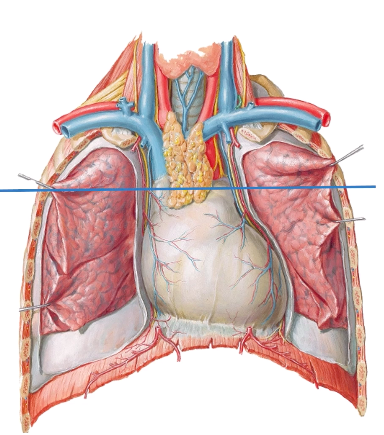

within the inferior mediastinum:

whats in the anterior mediastinum?

whats in the middle mediastinum?

whats in the posterior mediastinum?

anterior mediastinum: thymus

middle mediastinum: pericardium and heart

posterior mediastinum: primary bronchi, oesphagus, descending aorta, thoracic duct and zygous veins